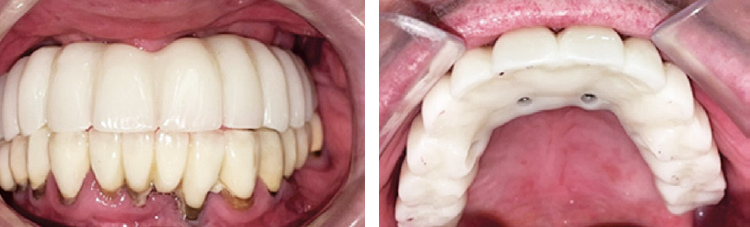

На рисунках 18, 19 изображены временные коронки в полости рта.

Рис. 18. Фотографии временных коронок на имплантатах в полости рта

Fig. 18. Photographs of implant-supported temporary crowns in the oral cavity